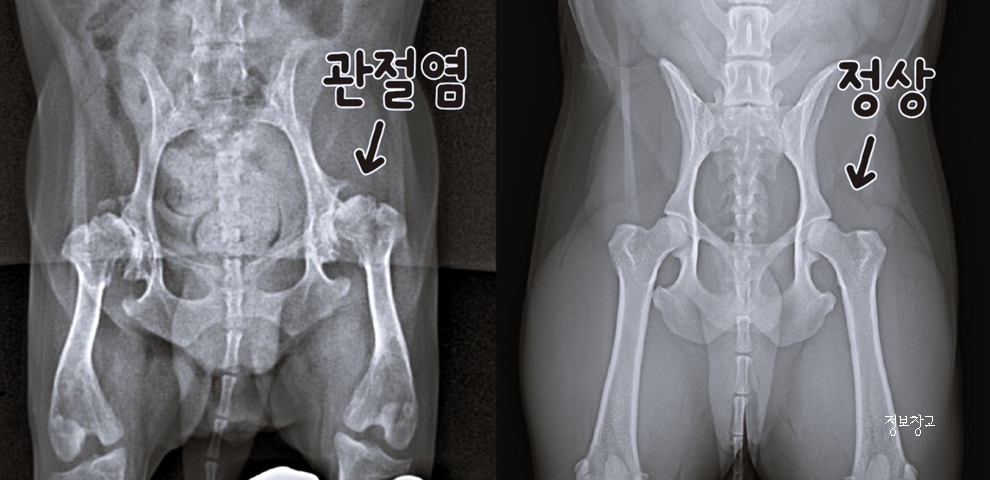

골절, 디스크, 관절염, 발바닥 상처 등도 원인이 될 수 있습니다.

7. 슬개골 탈구, 방치하면 어떻게 될까요?

초기에는 가볍게 보일 수 있지만

방치 시 다음과 같은 문제로 이어질 수 있습니다.

- 만성 관절염